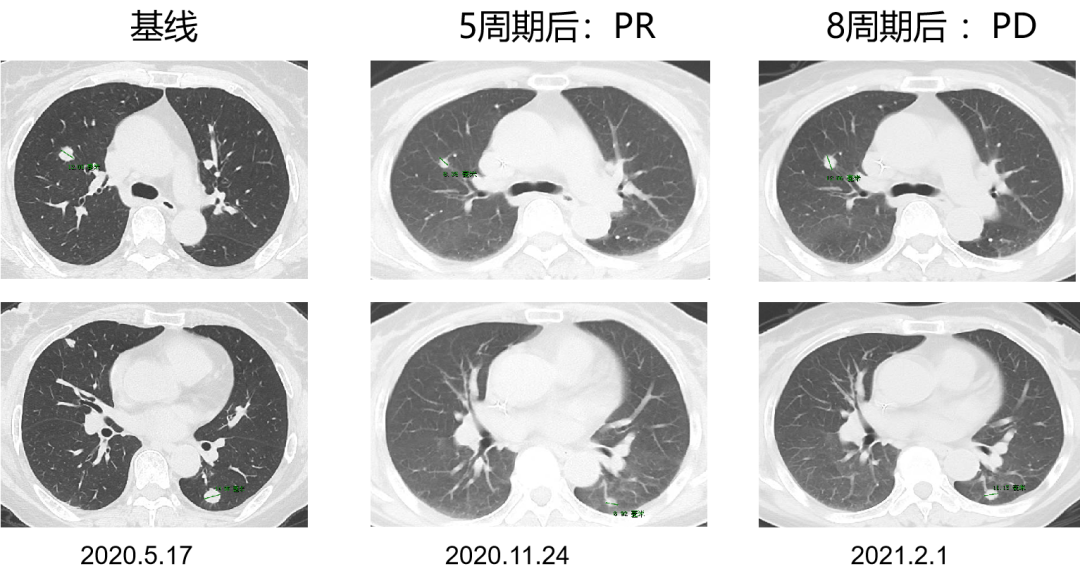

一 专家访谈 专家简介 于国华 教授 潍坊市人民医院 潍坊市肿瘤防治中心主任、潍坊市人民肿瘤医院院长、GCP机构副主任 潍坊市科技智库首席专家,省级重点学科负责人 中国临床肿瘤学会(CSCO)理事 山东省抗癌协会常务理事 潍坊市抗癌协会理事长 中国老年学学会舒缓治疗分会常务委员 中国老年学学会老年肿瘤专业委员会 中国老年学学会老年肿瘤专业委员会(CGOS)分子靶向分委会、肺癌分委会常务委员 山东省医学会肿瘤微创治疗分会副主任委员 山东省医学会姑息医学分会副主任委员 山东省肿瘤微创质量控制中心副主任委员 山东省医师协会肿瘤化疗医师分会副主任委员 山东省抗癌协会肿瘤化疗分会、肺癌分会、靶向治疗分会、心理治疗分会副主任委员 潍坊市医学会肿瘤化疗分会主任委员 潍坊市中西医结合学会肿瘤专业委员会主任委员 潍坊市肿瘤化疗专业质量控制中心主任 Q1 随着检查手段不断丰富,晚期结直肠癌的全程管理成为必然趋势。请您谈一谈我国在结直肠癌全程管理方面取得了哪些成果,未来应该朝着哪些方向努力? 我国在结直肠癌全程管理方面的进步成果,大概可以分为三个方面。 第一方面,随着医疗检测技术和诊疗理念的革新,我国早筛早治取得了良好进展。60~80年代我国检查技术相对落后,主要为粪便潜血试验展开有关肠道检查,而随着内镜技术的发展,肠镜检查逐渐普及,提高了结直肠癌早期患者的诊断率,推进了我国早诊早治的策略,使更多患者及早发现疾病并接受治疗。 第二方面,我国医疗制度具有优越性。随着我国全民医保的全面落实,“全民健康”理念的普及,就诊路径日益优化,更加快速便捷,使患者尽早获得诊断和治疗。 第三方面,国家癌症中心以及有关学协会的成立,推动了我国整体诊疗水平的不断提高。不仅为基层和各级医院搭建了良好的学习平台,推动了临床医生的再学习、再教育,也使得规范化诊疗、多学科协作(MDT)等优秀诊疗理念得以推广和实践。 第四方面,在内外科领域,药物治疗和手术治疗也是发展比较迅速。我国加速推进新药研发和医药服务创新,使更多药物尽快落地,惠及我国患者。相有关学协会积极组织形成了具有实践和指导意义的全程管理专家共识/指南,包括患者自身情况的评估、围手术期管理、治疗药物的选择、各线药物治疗方案、药物不良反应管理等。 关于结直肠癌全程管理未来的发展,需要以预防、规范化治疗和新药研发为抓手。 第一方面,预防是结直肠癌管理的第一步,未来有待在国家层面开展大规模的宣传教育,科普健康生活方式,令群众了解结直肠癌危险因素,从源头降低结直肠癌的患病风险。 第二方面,早筛早诊尽管已经取得显著成效,等仍需要深入基层,覆盖偏远贫困地区,使更多结直肠癌患者能够在早期发现,尽早干预,提升结直肠癌患者整体生存和预后。 第三方面,结直肠癌诊疗规范有待进一步提升,尤其需要在基层医疗单位加强规范化诊疗的理念。 第四方面,精准医学时代背景下,我们希望未来随着分子水平研究和精准医学研究的进展,在疗效监测和复发监测方面能使用更精准、更有价值的分子标志物动态监测。在手术前判断患者是否需要先做辅助化疗,在手术后判断是否需要进行复发监测,通过分子标志物可以更早地提示未来是否会复发,是否需要提前干预,如果复发,分子标志物可以再次作为监测指标指导治疗。 第五方面,我们还需加大研发力度,开发更多新机制、新靶点的药物,进一步提升晚期结直肠癌的疗效。 Q2 长期以来,化疗始终是肿瘤治疗领域的基石。其中,曲氟尿苷替匹嘧啶片(TAS-102)作为新型口服化疗药,问世以来不断为结直肠癌领域打开新的治疗格局,请您谈谈该药在中国的上市是基于怎样的研究成果? TAS-102在中国的获批是基于国际多中心 RECOURSE 研究和亚太TERRA研究的结果。RECOURSE研究是TAS-102的国际多中心Ⅲ期临床研究,显示TAS-102较安慰剂显著延长中位OS时间(7.1个月对比5.3个月)和中位PFS时间(2.0个月对比1.7个月),死亡风险和疾病进展风险分别降低32%和52%。此后,有众多中国临床专家参与的TERRA研究,证实了TAS-102在亚洲人群的安全性和有效性,TERRA研究重复出了RECOURCE研究的结果,TAS-102组患者的中位OS时间(7.8个月对比7.1个月)和PFS时间(2.0个月对比1.8个月)得到显著改善,死亡风险和疾病进展风险分别降低21%和57%。这两项关键研究成功改写了包括ESMO、NCCN、CSCO等中外权威指南的推荐。 而且,这两项研究中,TAS-102的不良反应均以血液学毒性为主,有症状的不良反应发生率低。鉴于其良好的安全性和耐受性,TAS-102与其他药物联合用于肠癌也在研究中进行了探索并取得了不错的结果。 Q3 晚期结直肠癌的发生通常预示着预后相对较差、患者生存期不长,但依然有治愈的可能,这关系到临床治疗用药方案的决策。今年上半年发布的CACA-RC指南推荐不适合强烈治疗患者应用TAS-102联合贝伐珠单抗,作为晚期不可切除结直肠癌姑息一线治疗方案。请您谈谈该推荐治疗对我国晚期不可切除结直肠癌的临床治疗产生了怎样的影响? 晚期转移性结直肠癌的标准化疗方案在指南中是以奥沙利铂或伊立替康为基础的FOLFOX和FOLFIRI方案,在此基础上,可以联合西妥昔单抗或贝伐珠单抗,但是,依旧有部分患者身体状况无法耐受加强化疗,少数患者因为高敏可能出现药物过敏,针对这一类患者,治疗方案的选择非常有限且预后情况并不理想。临床上往往推荐口服化疗药物+贝伐珠单抗方案。 2022年CACA-RC指南基于TASCO1研究的结果,推荐拒绝静脉化疗或不能耐受强烈治疗、易敏的晚期肠癌患者姑息一线选择TAS-102+贝伐珠单抗方案。TASCO1研究是一项旨在随机比较TAS-102+贝伐珠单抗和卡培他滨+贝伐珠单抗在一线治疗不可接受强烈治疗的不可切除转移性结直肠癌的Ⅱ期研究。研究结果显示:TAS-102组延长患者mPFS时间1.41个月(9.23个月对比7.82个月);延长患者mOS时间4.64个月(22.31个月对比17.67个月)。安全性分析也提示TAS-102+贝伐珠单抗治疗具有良好的耐受性,它最常发生的3/4级不良事件是中性粒细胞减少症。严重的发热性中性粒细胞减少症发生率约为4%。TAS-102+贝伐珠单抗方案因其高效、低毒的特点为不适合强烈治疗的转移性结直肠癌患者及老年患者带来了新的希望,其疗效与生存获益令人期待。 Q4 近年来,结直肠癌领域联合治疗的研究探索不断取得进步。请您谈谈,还有哪些研究进展为TAS-102联合贝伐珠单抗奠定一线治疗地位打下基础? 近年来,多项临床研究不断为TAS-102的临床可及性打下良好基础,DANISH研究将TAS-102与贝伐珠单抗联合用于转移性结直肠癌二线及以上治疗,发现联合组较TAS-102单药组疗效更好,中位PFS时间(4.6个月对比2.6个月)和OS时间(9.4个月对比6.7个月)显著延长,且联合组安全性可控,未出现非预期的不良反应。日本C-TASK-FORCE研究和欧洲DANISH研究均显示,对于PS为0~1分的转移性结直肠癌患者,TAS-102+贝伐珠单抗三线治疗实现了超过4.5个月的中位无进展生存期(PFS),超越了既往单药三线治疗的总体水平,且未显著增加不良事件(AEs)。TAS-102+贝伐珠单抗4周方案治疗转移性结直肠癌显示了良好的抗肿瘤活性。日本BiTS研究确证了双周方案可在不影响疗效的前提下,明显降低中性粒细胞减少症发生率。日本KSCC 1602研究和欧洲TASCO1研究都成功探索了FTD/TPI+贝伐珠单抗用于转移性结直肠癌一线治疗的疗效和安全性。 二 病例分享 专家简介 任海朋 主任 潍坊市人民医院 潍坊市人民医院肿瘤内科副主任,副主任医师 中国抗癌协会肿瘤微创治疗专业委员会委员 中国抗癌协会肿瘤消融治疗专业委员会委员 山东省健康管理协会消化道肿瘤防治分会副主任委员 山东省抗癌协会青年理事会常务理事 山东省医学会肝脏肿瘤多学科联合委员会委员 山东省抗癌协会消化道肿瘤分会委员 潍坊市医学会结直肠癌多学科联合专委会副主任委员 潍坊市医学会肿瘤微创治疗专业委员会副主任委员 潍坊市医师协会肿瘤化疗医师分会副主任委员 肖海凤 医师 潍坊市人民医院 潍坊市人民医院肿瘤内科主治医师,硕士 山东省抗癌协会化疗分会青年委员会委员 山东省疼痛医学会癌痛与姑息治疗专业委员会委员 山东省医学会科学普及分会肿瘤科普学组委员 山东省医学会精准医学分会消化道肿瘤学组委员 潍坊市医学会化疗专业委员会委员兼秘书 潍坊市抗癌协会乳腺癌专业委员会委员 潍坊市抗癌协会妇科肿瘤分会委员 潍坊市医学会第三届肛肠外科专业委员会青年学组委员 01 基本情况 基本情况:史xx,女,57岁,既往体健,无特殊病史,无家族史。 简要病史: 2020.1 患者出现大便带血,为暗红色,与大便相混,伴大便次数增多3~4次/天,大便不成形,伴肛门坠胀及里急后重感。 2020.4 就诊于潍坊市人民医院消化内科门诊,行肠镜示距肛门10cm环周隆起性病变,肠腔狭窄,镜身不能通过,考虑直肠癌,活检病理示腺癌(中分化)。 2020.4.16 就诊于我院肛肠外科一区,行胸腹盆部CT提示乙状结肠占位,考虑肿瘤,盆腔肿大淋巴结,双肺多发转移瘤。 诊断:直肠癌(cT3N+M1a,IVa期)。 2020.4.18 肺多发转移(CT) 2020.4.18 直肠原发灶(CT) 2020.5.12 基因检测 KRAS:Exon2、Exon3无突变;NRAS:Exon2、Exon3 无突变;BRAF:Exon15(V600E)无突变。UGT1A1*28:TA6/7,UGT1A1*6:G/G。MSS。 02 治疗经过 因直肠原发灶进镜困难,肠腔狭窄,发生肠梗阻风险较大,建议先行原发灶切除,后行全身抗肿瘤治疗。 2020.4.23 行直肠癌根治术(前切除术)+回肠预防性造口术+肠粘连松解术。 术后病理 一线治疗经过 2020.5.18至2021.1.31 行奥沙利铂甘露醇注射液225mg d1+卡培他滨1.5g bid d1-14方案化疗8周期。 不良反应:胃肠道反应不著,骨髓抑制最重2度。 疗效评价:5周期后疗效评价为PR,8周期后疗效评价为PD。 双肺转移灶(一线) 二线治疗经过 入住我科,ECOG 0分,身高159cm,体重65kg,体表面积1.64m2。 2021.3.9、2021.3.29、2021.4.12、2021.5.6、2021.5.25、2021.6.21、2021.7.9、2021.7.28、2021.8.15行西妥昔单抗800mg d1+伊立替康300mg d2+氟尿嘧啶650mg iv,4000mg civ 46h+左亚叶酸钙325mg d2化疗9周期。 不良反应:胃肠道反应不著,骨髓抑制2度。 疗效评价:缩小的SD。 双肺转移灶(二线) 三线治疗经过 2021.9至2022.5.6 口服呋喹替尼5mg qd d1-21 q28d治疗。 不良反应:高血压病1级,轻度肝功损伤。 疗效评价:2个月后疗效评价PR,7个月后肺内病灶增大,肝内出现新发病灶,疗效评价PD。 双肺转移灶(三线) 肝脏(新发病灶) 四线治疗经过 2022.5至今 开始应用贝伐珠单抗300mg d1联合TAS-102 55mg bid d1-5双周治疗。 不良反应:高血压2级,继发性甲状腺功能减退,白细胞减少I度,中性粒细胞减少2度,贫血1级。 疗效评价:PR。 03 病例小结 04 心得体会 TAS-102是一种新型口服细胞毒药物,是口服的氟尿嘧啶类药物,作用机制不同于氟尿嘧啶,可用于氟尿嘧啶耐药患者。 国际RECORSE和亚太TERRA研究证实,TAS-102在mCRC治疗中具有一致的疗效和安全性:1.显著延长mCRC患者生存期,降低死亡和疾病进展风险,尤其对于≥65岁患者获益更显著;2.显著延缓体能下降,为持续治疗提供体能储备;3.主要不良事件为血液学毒性。 双周TAS-102联合贝伐单抗不仅不降低疗效,而且明显降低中性粒细胞减少症发生率。 *本文仅代表专家观点,并经专家审校。